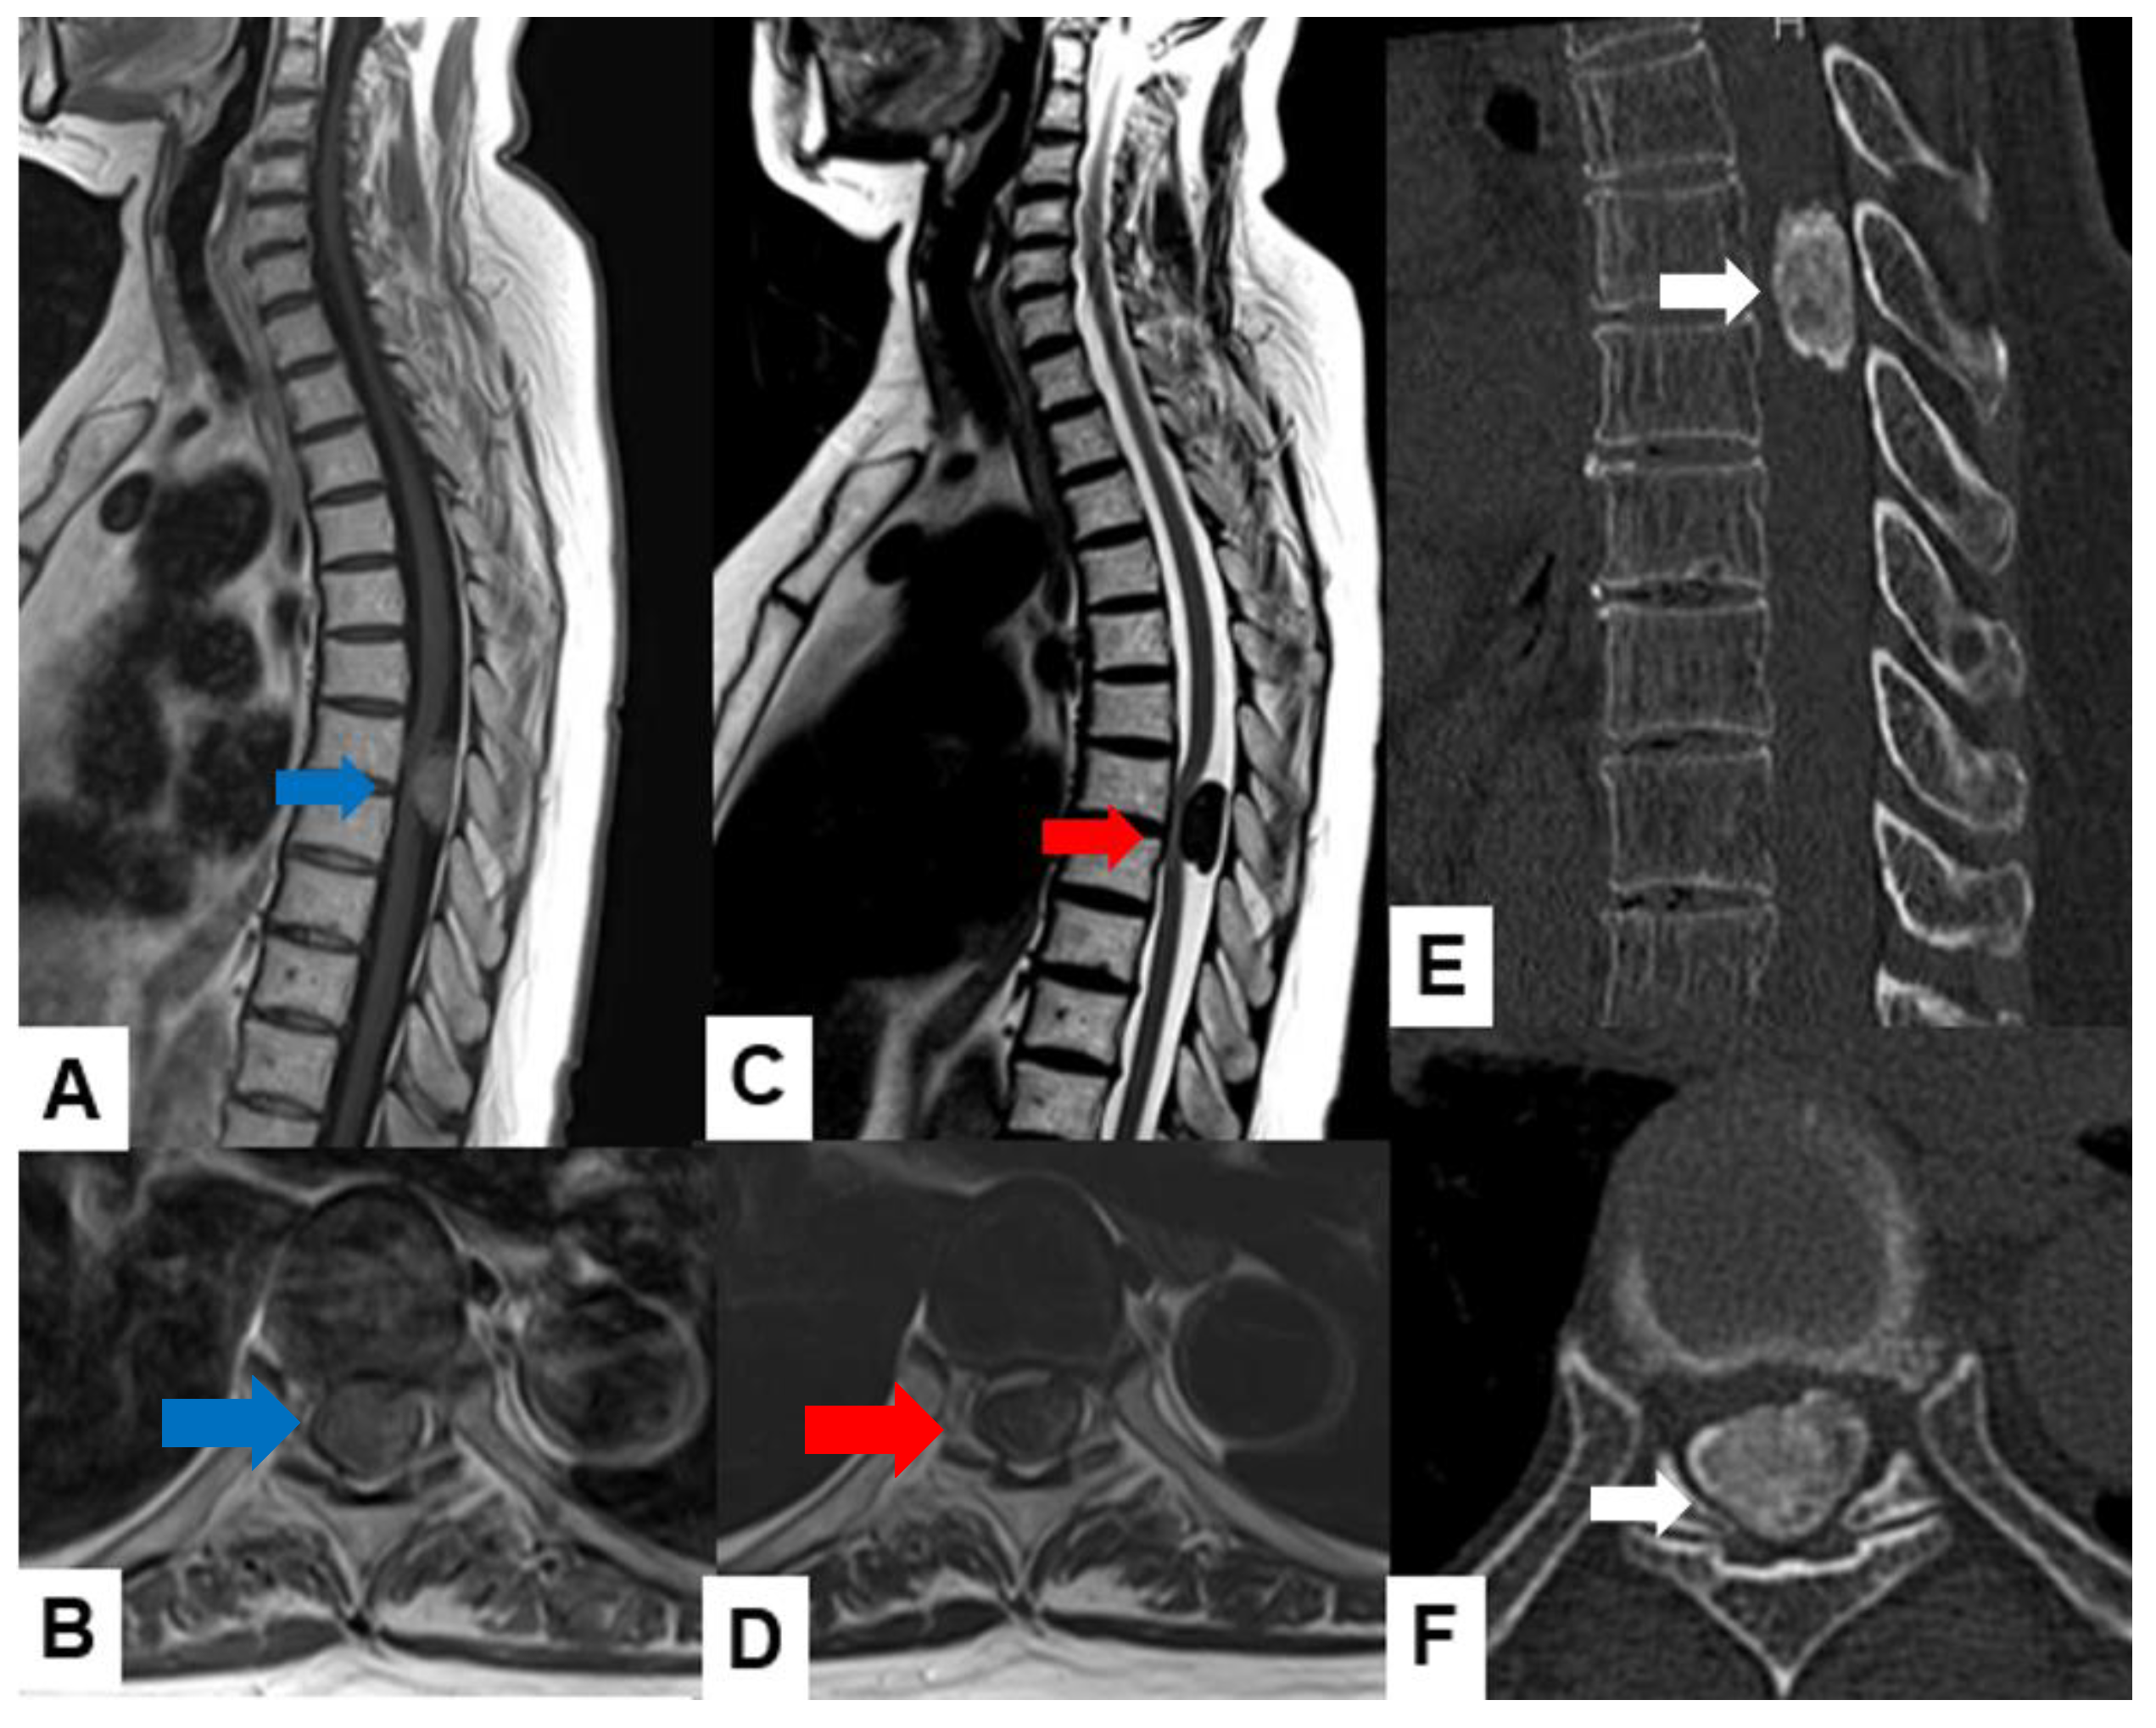

Ependymoma: Myxopapillary ependymomas typically present as well-defined intradural extramedullary masses with a heterogeneous signal intensity in T1-weighted images and hyperintensity in T2-weighted images (Figure 6). These tumors often demonstrate avid contrast enhancement.

Figure 6.

Thirty-seven M, spinal ependymoma, grade 1. (A) T1-weighted midsagittal image, (B) T1-weighted axial image at C4/5, (C) T2-weighted midsagittal image, (D) T2-weighted axial image at C4/5, (E) enhanced T1-weighted midsagittal image, and (F) enhanced T1-weighted axial image at C4/5. Red arrows indicate tumor; blue arrow shows enhancement. Green arrows indicate large syringomyelia.